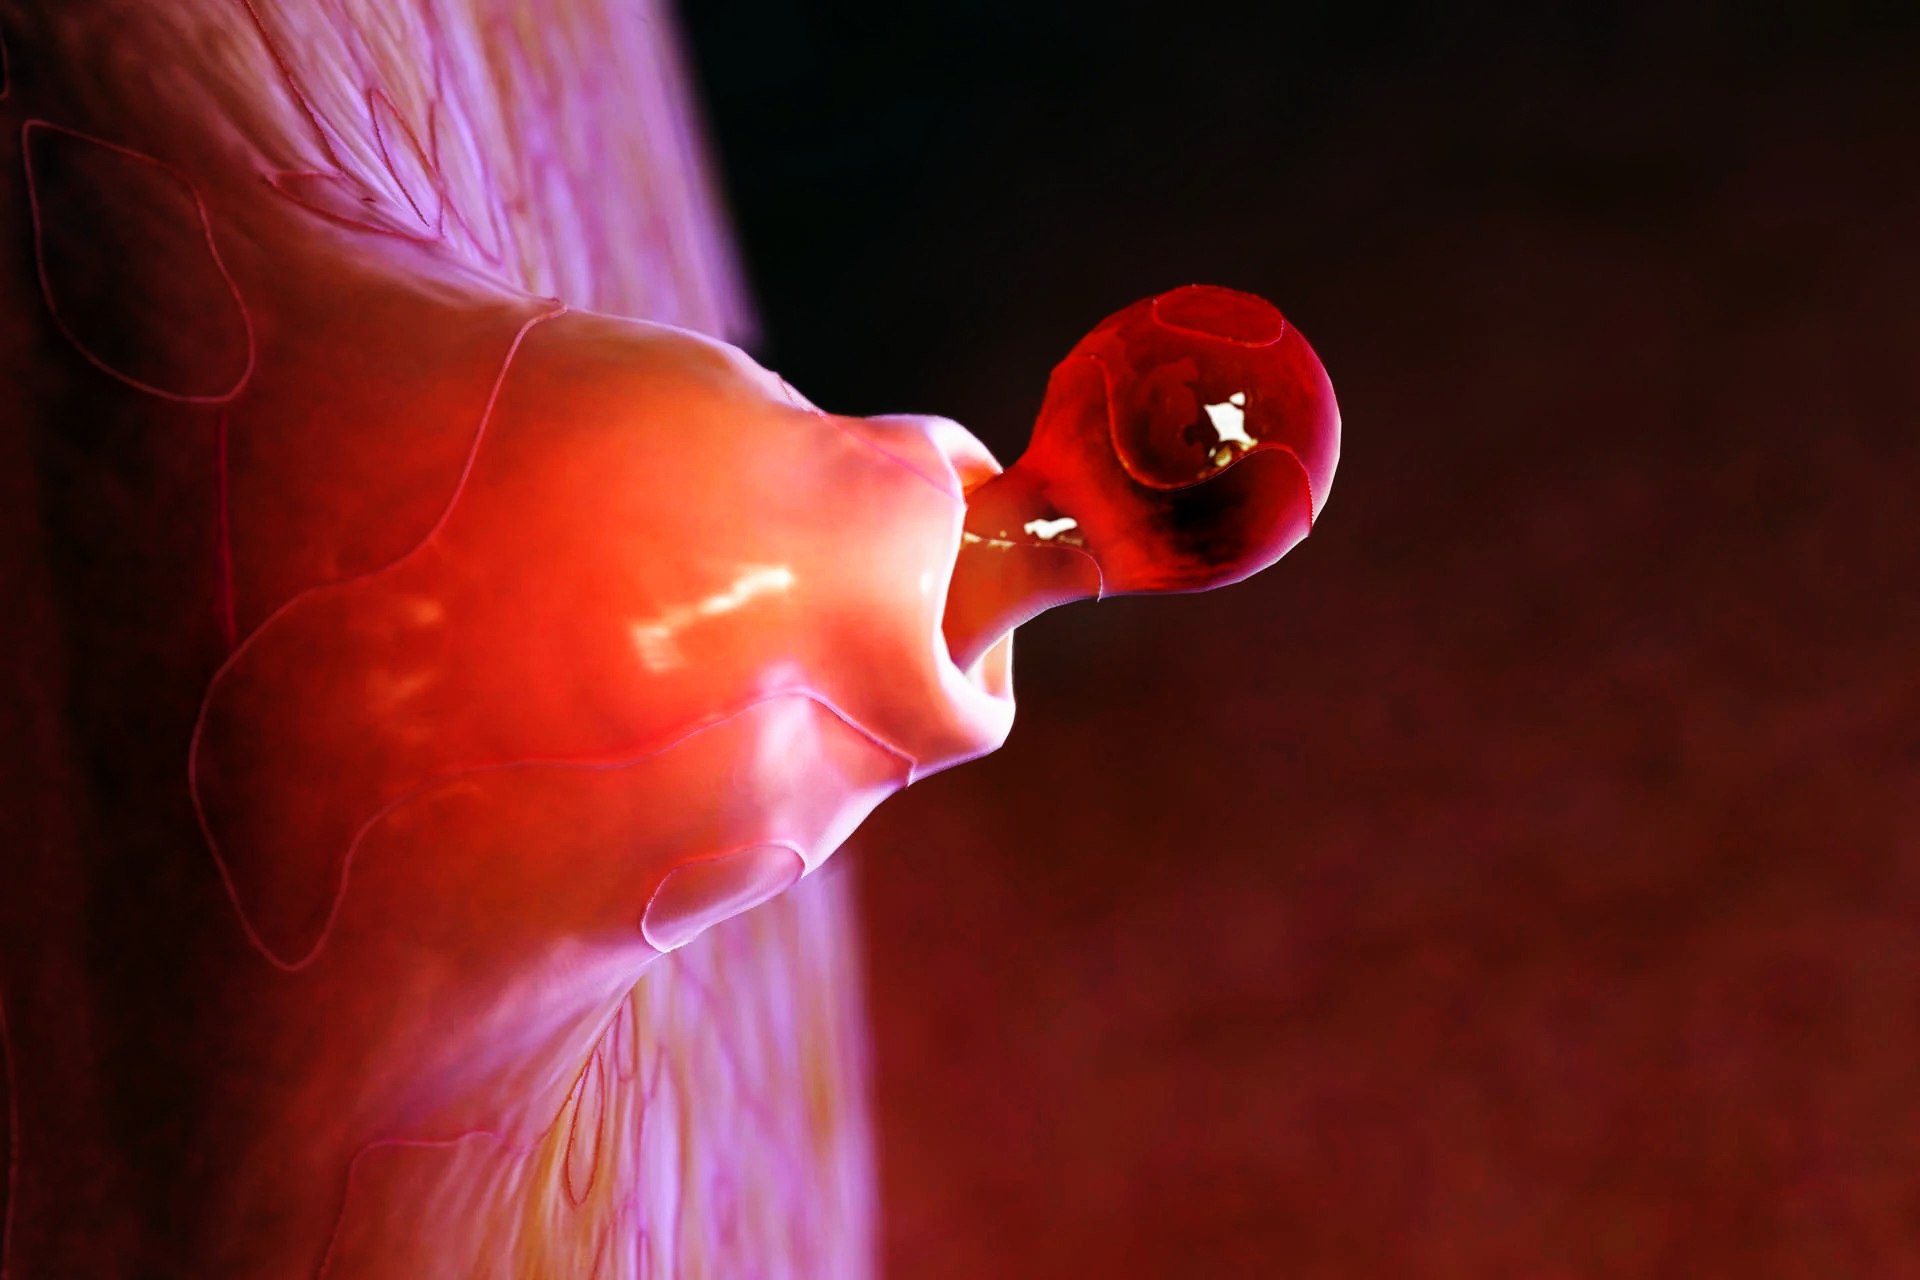

Созревание фолликула в яичнике: этапы и процессы